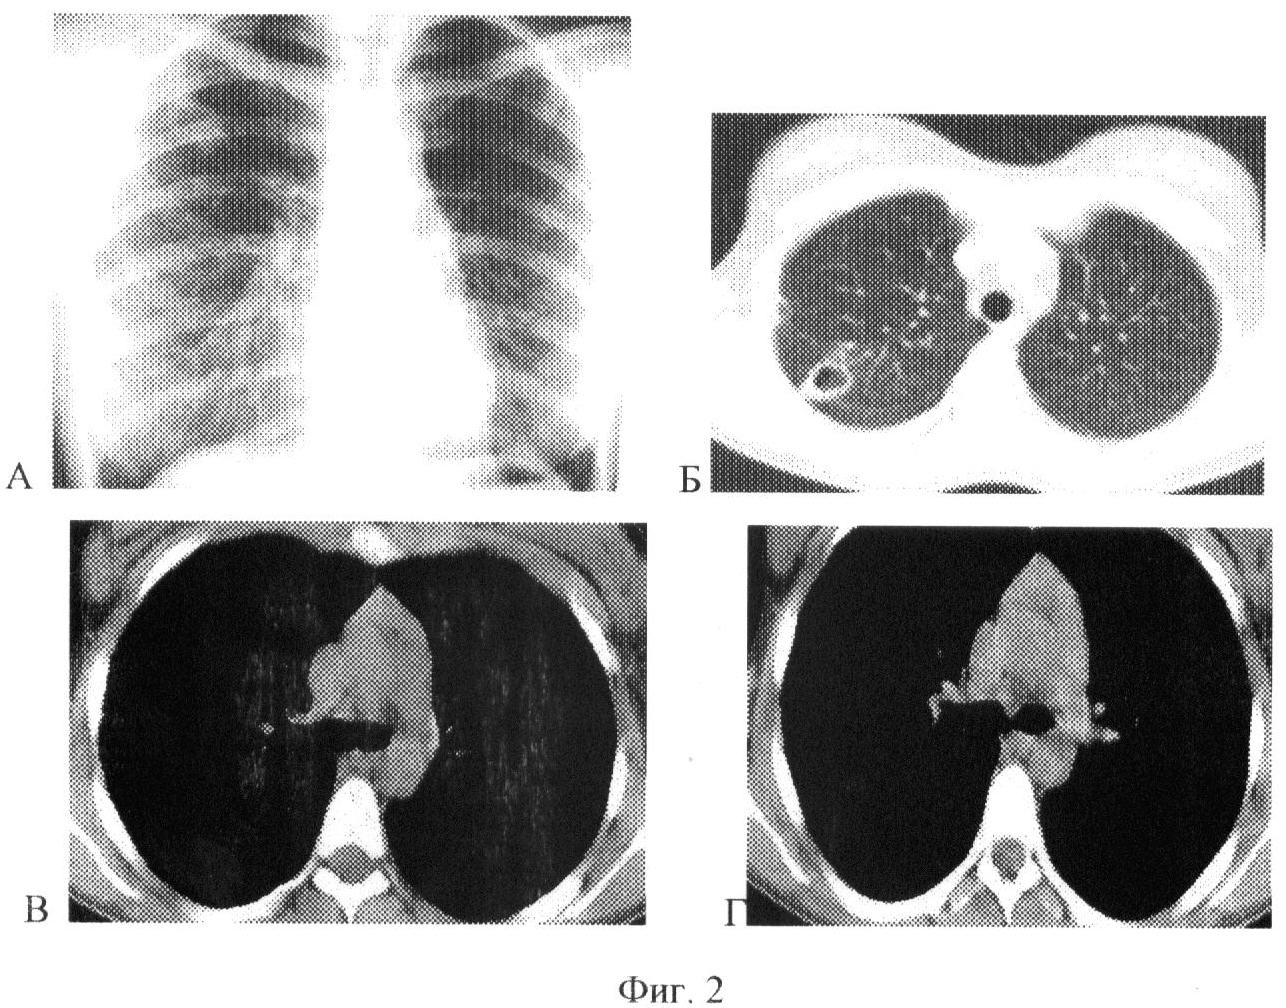

Сущность предлагаемого изобретения представлена на фиг.1, 2 и 3. На фиг.1 – данные рентгенологического обследования больного (пример 1), на фиг.2 и 3 – данные рентгенологического обследования больного (пример 2).

1. Пациент Г., 36 лет, поступил в терапевтическое отделение СПбНИИФ 09.01.2007 года с диагнозом инфильтративный ТВС в/д правого легкого в фазе распада БК+. Из анамнеза известно, что туберкулезом болен с января 2006 года с волнообразным течением процесса. Несмотря на длительную интенсивную полихимиотерапию сохранялась бактериовыделение и полость распада (каверна) в верхней доле правого легкого. Выявлена множественная лекарственная устойчивость микобактерий туберкулеза.

При рентгенологическом обследовании от 29.03.07 (Фиг.1-А, Б) отмечается сохранение полости распада (каверны) со сформированной стенкой в S2 правого легкого размером 2,4×3,6 см, на фоне фиброзно-перестроенного легочного рисунка и разнокалиберных очагов. Дополнительно визуализируются (Фиг.1-В, Г) увеличенные до 1,3 см в наибольшем размере лимфоузлы правой трахеобронхиальной и бронхопульмональной группы. Структура лимфоузлов неоднородна за счет участков повышенной плотности в центральных отделах лимфоузла. Неоднородность структуры позволяет сделать вывод о туберкулезном лимфадените.

11.04.2007 года в связи с неэффективностью консервативной терапии произведена операция – правосторонняя верхняя лобэктомия с лимфодисекцией трахеобронхиальных и бронхопульмональных лимфоузлов справа. Гистологическое заключение: Фиброзно-кавернозный туберкулез верхней доли правого легкого. Туберкулезный лимфаденит.